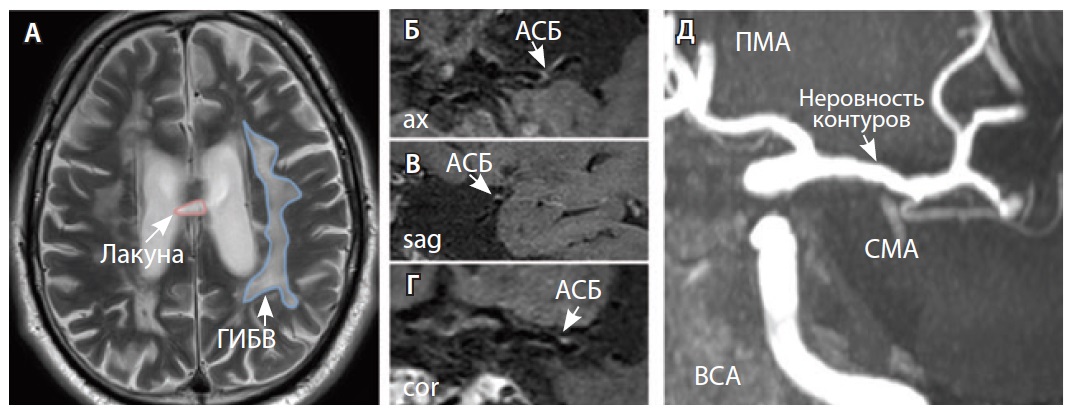

Рис. 3. Пациент Ц., 53 года, с признаками церебральной микроангиопатии (F3 по шкале Fazekas), атеросклерозом интракраниальных артерий, без формирования гемодинамически значимых стенозов. А – магнитно-резонансная томография (МРТ) головного мозга, режим Т2-взвешенного изображения: видны обширные сливные зоны гиперинтенсивности белого вещества (ГИБВ) с наличием на этом фоне лакунарных инфарктов; Б, В, Г – МРТ сосудистой стенки, режим T1-TSE-db-FS после контрастного усиления: в сегменте М1 левой средней мозговой артерии (СМА) визуализируется эксцентричная атеросклеротическая бляшка (АСБ), интенсивно накапливающая контрастный препарат; Д – трехмерная магнитно-резонансная времяпролетная (3D ToF) ангиография: выявляется неровность контуров левой СМА в сегменте М1; ax – аксиальная, sag – сагиттальная, cor – коронарная плоскости; ВСА – внутренняя сонная артерия; ПМА – передняя мозговая артерия